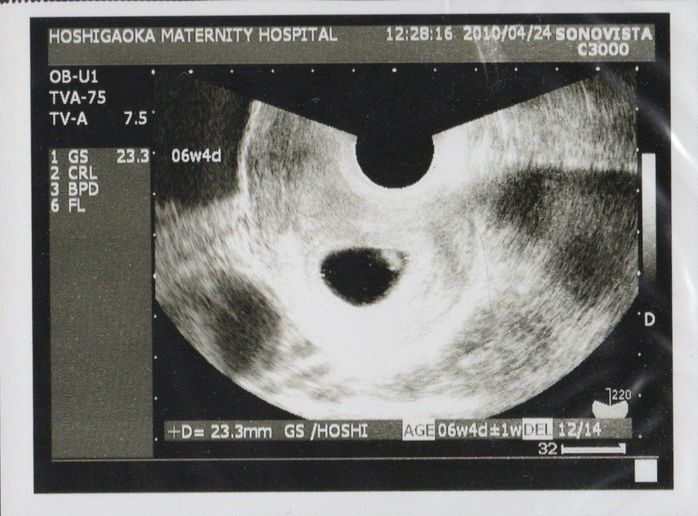

妊娠6週目のエコー写真

初めての健診で、胎嚢の中にいる我が子が確認できました。心拍もしっかりしていたので、医師から「おめでとうございます」と言われ、妊娠が確定しました。まだ23.3mmしかない小さな袋の中の胎芽(妊娠8週未満の赤ちゃんのこと)に、生命誕生の凄さを感じました。